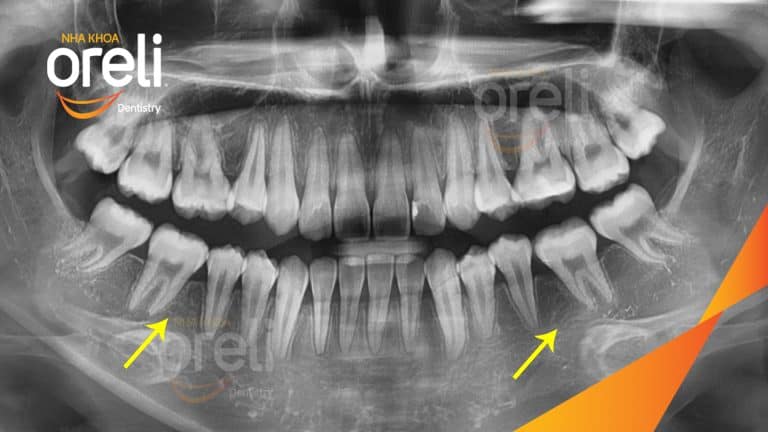

Ca niềng chỉnh hô nhổ 2 răng 4 hàm trên di gần răng 7 8 hàm dưới cho nụ cười đẹp – Kết quả sau hơn 2 năm ở Oreli Niềng răngDi gần răng 7 8Hô Xem thêm